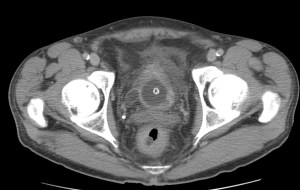

Se realiza nueva TC bifásico abdominopélvio y Uro TC.

- Paciente con numerosas recidivas por Cá vejiga.

- Ha desarrollado un tumor metacrónico en pelvis renal derecha, también responsable de la hidroureteronefrosis.

- Mala evolución radiológica del proceso a expensas de metástasis pulmonares y hepáticas.